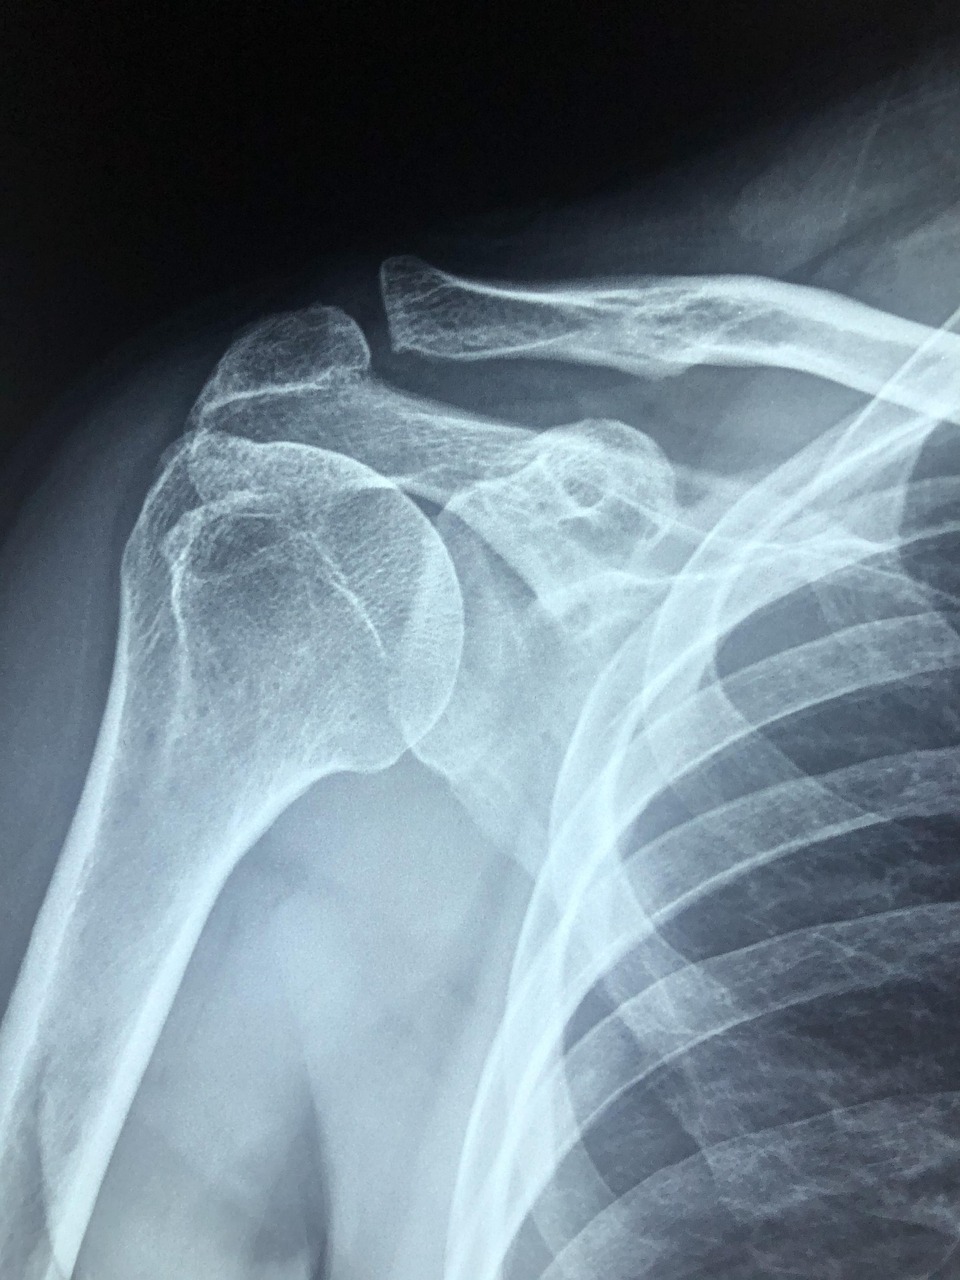

많은 분들이 병원을 찾으면 물어보는 질문 중 하나입니다. 특히 오십견, 회전근개 손상, 석회화건염 등으로 인해 어깨 통증이 극심할 때, 스테로이드 주사가 빠른 통증 완화를 돕는다고 알려져 있습니다.

스테로이드 주사는 흔히 ‘염증 주사’라고 불리며, 염증 반응을 줄여 통증을 빠르게 완화하는 데 큰 역할을 합니다. 특히 어깨 통증의 원인 중 상당수는 염증 반응과 관련이 있습니다. 오십견(유착성 관절낭염), 회전근개 손상, 석회화건염 등은 모두 어깨 관절 내 조직에 염증이 발생하면서 통증과 운동 제한을 유발합니다. 이때 스테로이드 성분이 염증 매개 물질을 억제해 부종 감소와 통증 완화를 이끌어내는 것입니다.